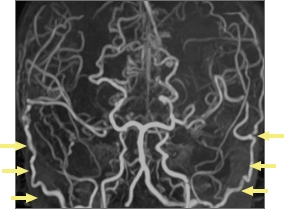

4歳女児症例 脳MRA検査

治療前

両側STAMCAバイパス術後